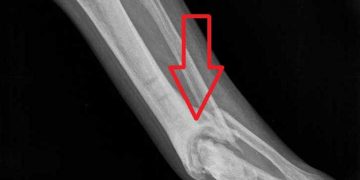

Yalancı Eklem, kırıkta hareketsizliğin sağlanamaması nedeniyle kırık uçlarının fibrokartilaj yapıda sert bir tabakayla örtülmesi ve kaynamanın olmayıp kırık uçlarının sanki ...